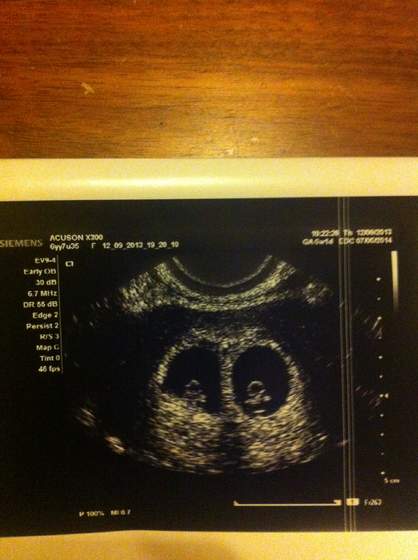

A to nasze pierwsze zdjęcie z USG - bliźnięta... Więcej nie napiszę, bo jestem w szokugeneralnie wszystko dobrze!

Dziękuję Wam za gratulacje, dziewczyny! Już powoli wychodzę z szoku, masakra jakaś - nie spodziewałam się bliźniąt!

Betę robiłam w trzecim tygodniu ciąży i była dość niska, jakieś 380 - więc dopiero teraz musiała skoczyć, powtórkę bety dopiero zrobię. Mam młodsze o 6 lat siostry bliźniaczki - dwujajowe, poza tym nie ma bliźniąt w mojej ani mojego D. rodzinie, w ogóle się nie spodziewałam, bo myślałam, że moje siostry ot tak się trafiły... A jednak

Zaszłam w ciążę naturalnie,w 3 cyklu. To moja pierwsza ciąża, mam 22 lata

Jeśli chodzi o lekarza - sprzęt ma chyba dobry, bo faktycznie pięknie widać. Chodzę prywatnie do mojego gina, jest świetny. Zapłacłam za całą wizytę i USG (ze zdjęciami) 100zł.